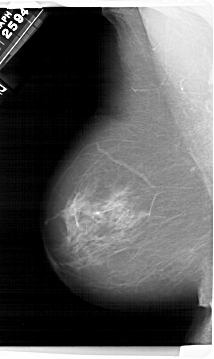

A_1495_1.LEFT_MLO

LEFT_MLO LINES 6811 PIXELS_PER_LINE 4066 BITS_PER_PIXEL 12 RESOLUTION 43.5 NON_OVERLAY